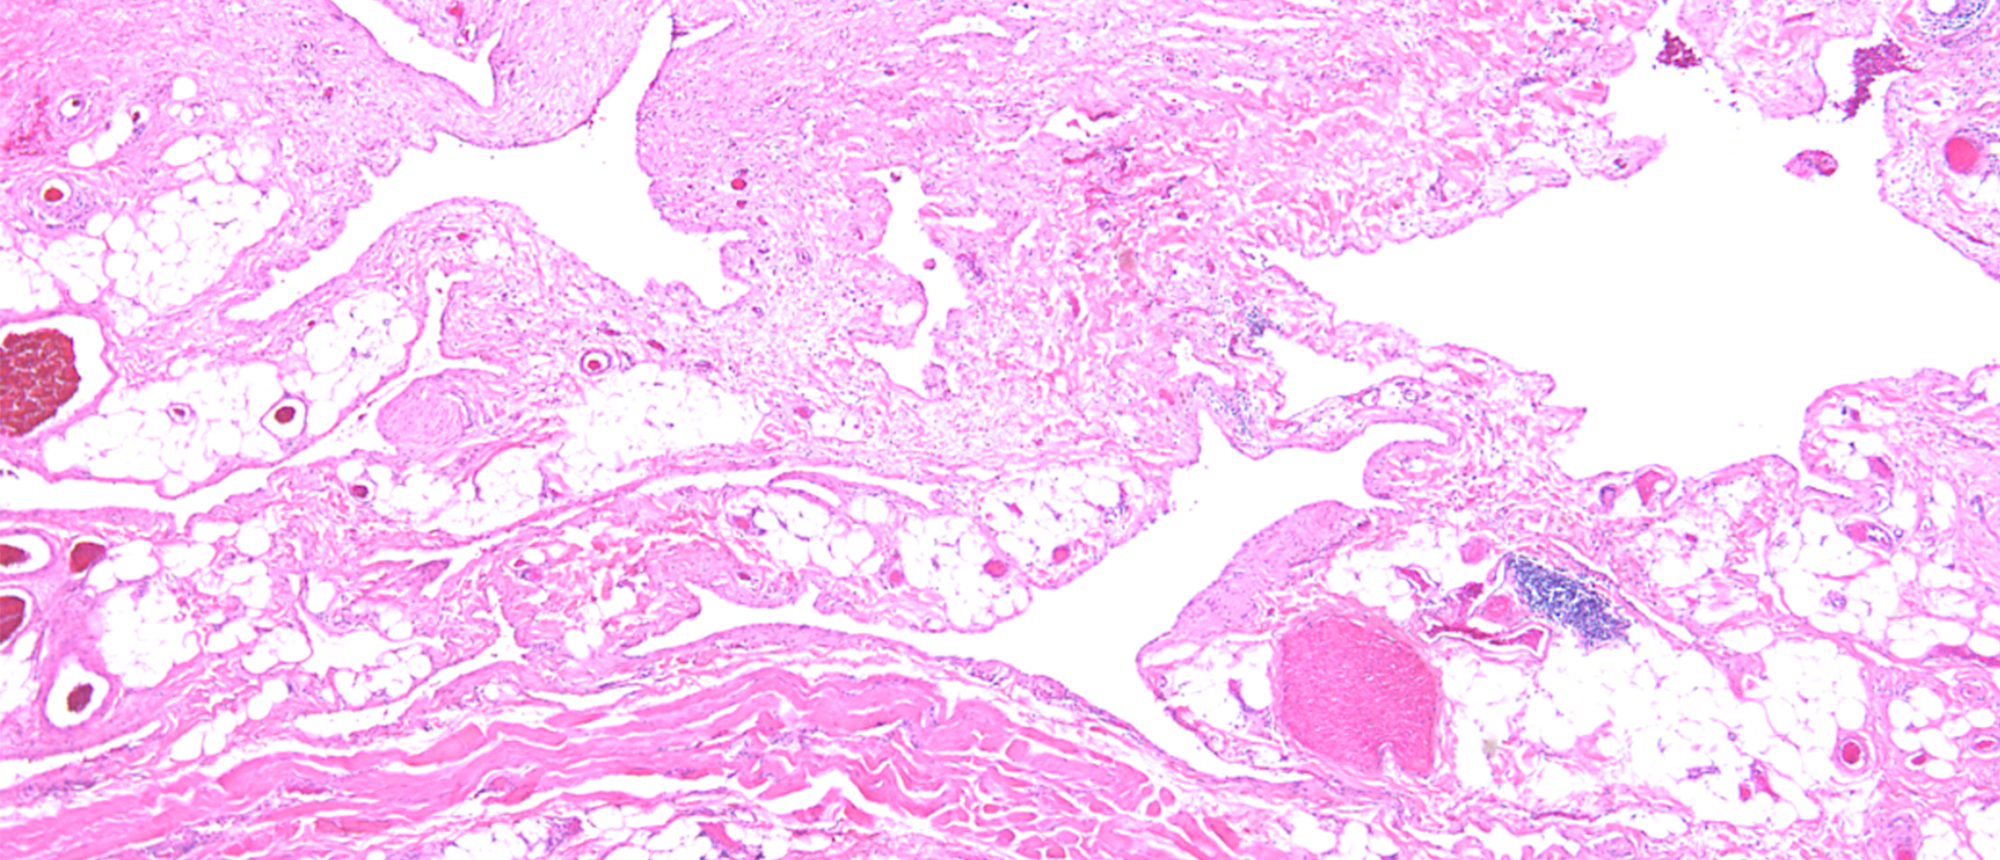

Abstract A patient with a past ocular history of HSV keratitis and chalazia s/p biopsy presented with severe light sensitivity and intermittent ocular redness and discomfort in OS with symptoms present for ~ 10-15 years. The slit lamp exam was notable for an elevated, gelatinous lesion located in a…

Secondary Corneal Amyloidosis A patient with a past ocular history of HSV keratitis and chalazia s/p biopsy presented with severe light sensitivity and intermittent ocular redness and discomfort in OS with symptoms present for ~ 10-15 years. The slit lamp exam was notable for an elevated, gelatinou…